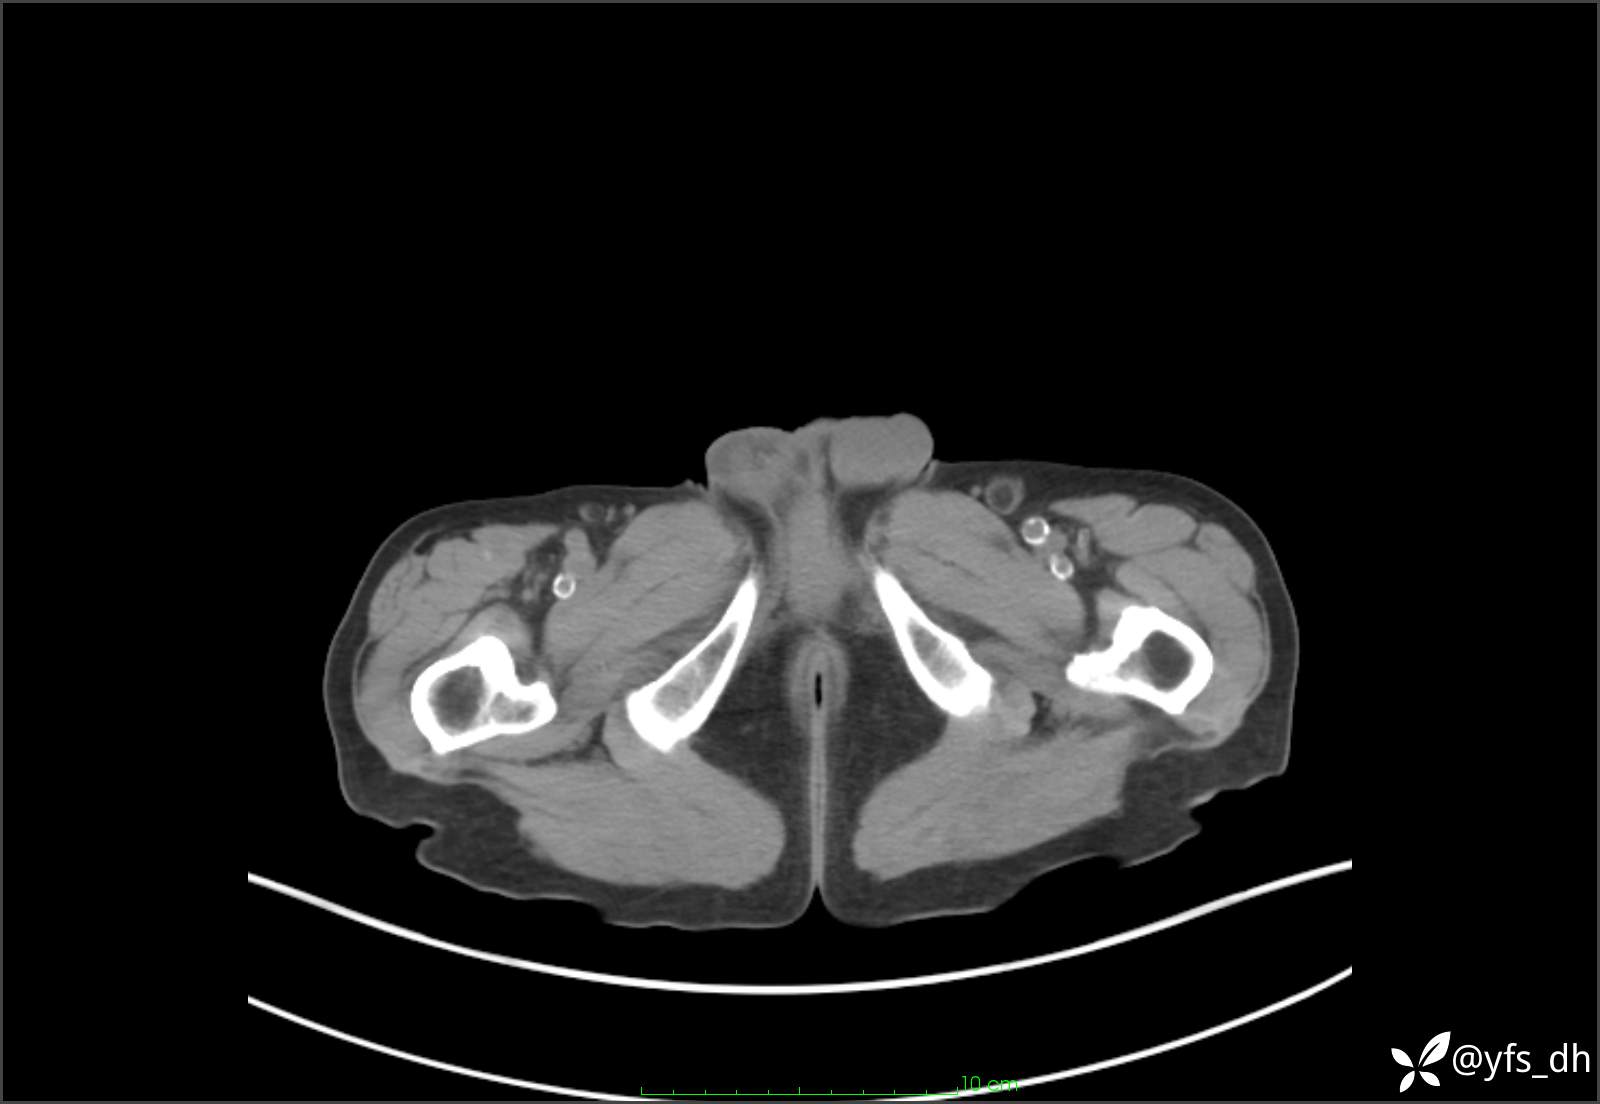

1.简要病史:患者4天前突发上腹部疼痛不适,但可以忍受。3小时前饭后突然加重,不能忍受后就诊。

2.简要手术记录:术中见腹盆腔大量肠液及粪便,乙状结肠中下段见一约3cm的破口。